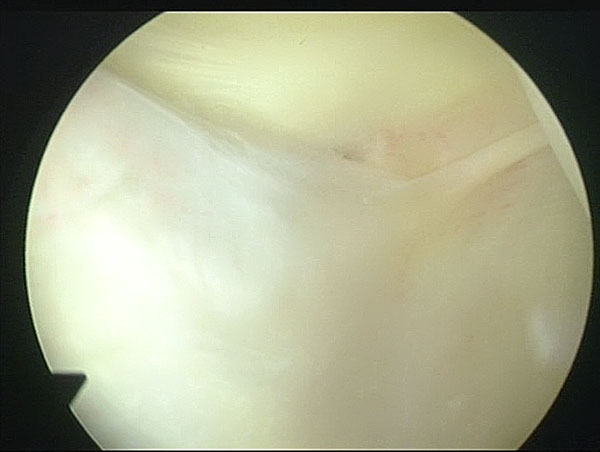

Arthroscopic Management of Baker's CYST